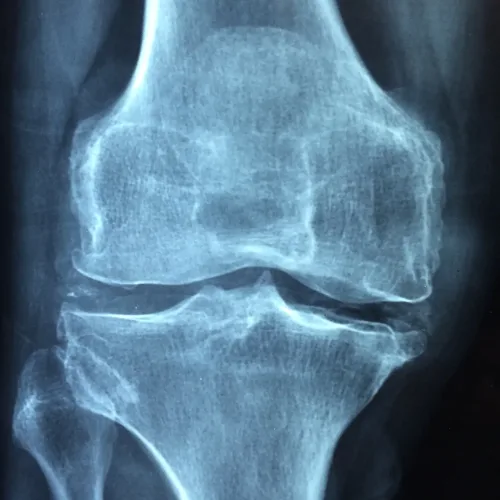

Osteoarthritis is a type of arthritis where the bone, cartilage and synovium wear down, leading to pain and stiffness. Synovium lines the joints and produces synovial fluid that lubricates the joins as well as supplies them with nutrients and oxygen. A 2016 study from the American Journal of Translational Research compared the effectiveness of acupuncture and physiotherapy for treating knee osteoarthritis. When looking at motor scores, pain, stiffness and physical function, those patients who received acupuncture had significantly improved scores compared to patients who received physiotherapy.